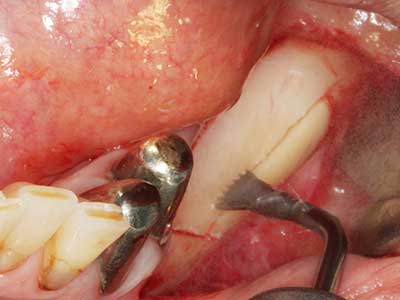

Come dimostrato in passato, pressoché qualsiasi procedura chirurgica che interessa il tessuto osseo rappresenta una possibile indicazione per la piezochirurgia. Quindi, per la preparazione del segmento mobile nella distrazione osteogenetica (figg. 23-25) e nell'osteotomia con tecnica a sandwich si utilizzano appositi raccordi per non danneggiare l'apporto sanguigno alla sezione della cresta, elemento essenziale per la corretta esecuzione di entrambe le tecniche (Gonzalez-Garcia, Diniz-Freitas et al. 2008).

Fig. 22: il segmento mobile può essere separato precisamente con la sega sottile per osteotomia (W&H Piezomed).

Fig. 23: mobilizzazione finale del segmento di distrazione del ramo palatale con il bisturi.

Fig. 24: applicazione del distrattore (TRACK-System, KLS Martin).